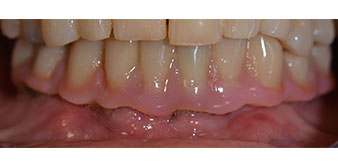

The impression and bite registration were then performed so that the dental technician could begin producing the provisional restoration immediately. This was then screwed in on the same day (Fig. 17 and 18).

Implants

Fig. 17

Fig. 18

Following the time required for the osseointegration, the final impression of the implants could be performed and the final denture produced accordingly (Fig. 19 and 20). At this point, the dentist and patient were able to decide together whether to use a ceramic or acrylic veneer and a zirconium or metal framework. In this case, Dr. Pascu’s team decided on an acrylic veneer based on the unclear prognosis for the maxillary dentition and the fact that tooth 24 is elongated. This type of veneer is generally considerably easier to adapt and can thus be subsequently altered to reflect the new situation in the maxilla.

Osseointegration

Fig. 19

Fig. 20